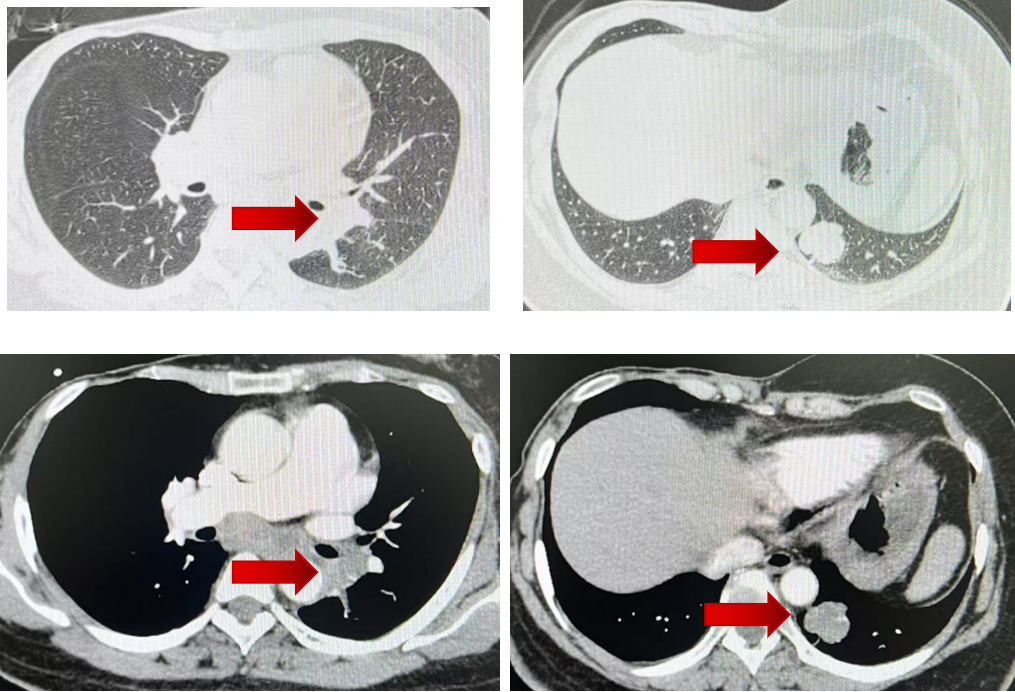

2024年1月胸部增强CT提示:左肺下叶占位,考虑恶性病变;左肺门区、纵隔淋巴结肿大。头颅MRI示左侧额顶叶陈旧性梗塞。骨扫描示脊柱部分椎体及附件、左侧膝关节及踝关节代谢不均匀活跃,多考虑良性病变。

初始疗效评价:2024年3月复查较2024年1月基线相比,病灶较前缩小,疗效评价为SD(伴肿瘤缩小)。

换用达尔西利联合阿那曲唑后,患者后续多次复查均提示病灶进一步缩小,2024年8月、2024年11月、2025年4月及2025年9月疗效评价均为PR。靶病灶总和由55 mm降至20 mm,整体缩小约63.6%,提示调整方案后患者获得了持续且稳定的影像学缓解。